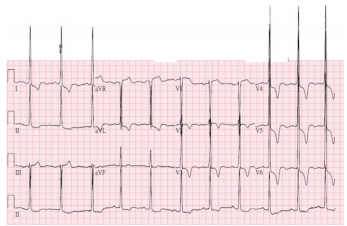

19. 一位82歲男性病患因骨頭壓痛,喘與腳腫至門診就診,血壓為96/60毫米汞柱,心跳每分鐘為80次,身體檢查呈現:結膜蒼白,頸靜脈怒張,兩側呼吸音減弱,心臟聽診左下胸骨呈現第三級收縮期雜音,並隨吸氣加重,心尖部呈現第三級收縮期雜音,兩側下肢明顯水腫。抽血檢查呈現BUN 70 mg/dl, cre 5.5mg/dl, Na 140 mmol/L, K 4.2 mmol/L, calcium 2.8 mmol/L, phosphate 5.3 mg/dL, Hb 10.7 g/dl, MCV 85.2 fL, WBC 9.61 k/uL, platelet 197 k/uL, albumin 3.1 g/dl, total protein 7.6 g/dl, 驗尿尿蛋白呈現3+, 頭骨X光呈現 punched-out病灶.骨髓切片檢查呈現明顯plasma cell neoplasm.醫師懷疑心臟也有被此疾病波及.請問下列心臟檢查結果,何者與這個懷疑較不吻合? (A) 心電圖A (B) 心電圖B (C) 心臟超音波呈現心肌肥厚與sparkling (D) 心臟超音波左心室出現restrictive filling pattern (E) 心臟超音波呈現中至重度三尖瓣膜閉鎖不全

圖 A